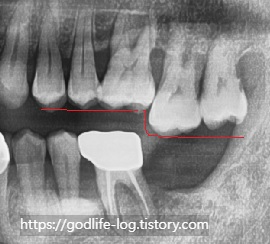

위 사진은 아랫치아를 발치 수 오랫동안 방치하여 맞물리는 치아가 없어서 윗 치아가 정출 된 상황입니다. 반대로 윗 치아가 없으면 아래치아가 위로 솟게 됩니다.

이렇게 치아가 많이 정출 된다면 치아 뿌리가 많이 드러날 수밖에 없고, 최악의 경우에는 윗 치아도 함께 발치를 해야 할 수도 있습니다.